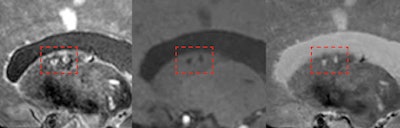

7-tesla MRI can detect the total burden of larger and smaller infarcts, including small microinfarcts in the deep gray matter (shown here inside red frames). Images are courtesy of Dr. Jeroen Hendrikse and originally appeared in ECR Today on 28 February 2019.

7-tesla MRI can detect the total burden of larger and smaller infarcts, including small microinfarcts in the deep gray matter (shown here inside red frames). Images are courtesy of Dr. Jeroen Hendrikse and originally appeared in ECR Today on 28 February 2019.Outside of gadolinium, a clinical session on 7-tesla MRI drew an overflowing crowd interested in hearing the experiences of a handful of clinical sites around the world using ultrahigh-field MRI. The higher signal-to-noise ratio of 7-tesla MRI and other technical benefits offer new insights into neuro and musculoskeletal imaging. Cardiovascular and abdominal MRI are thought to be the next applications to benefit from 7-tesla scanning.